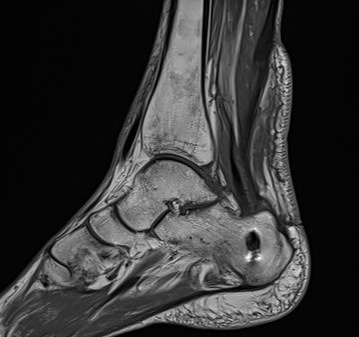

MRI

Tendon thickening, Haglund's deformity and retrocalcaneal bursa

Arthrex speedbridge system

Zadek osteotomy

Dorsal closing wedge osteotomy

Technique